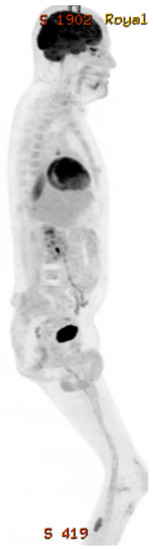

2. Case Presentation